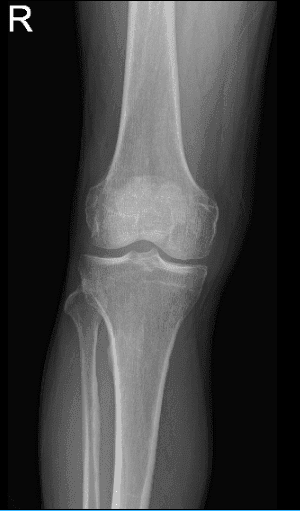

The patient is 66 years of age and came into the office with complaints of right knee pain. He remembered that he experienced the pain on and off a year ago. Patient denies remembering an injury that occurred. His knee X-ray showed no fractures and normal radiographs that’s why we agreed to take an MRI.

MRI of right knee

His MRI showed an impression as follows: Tricompartmental degenerative changes. Horizontal tear involving the body and posterior horn medial meniscus. Mild distal quadriceps tendinosis, without tears.